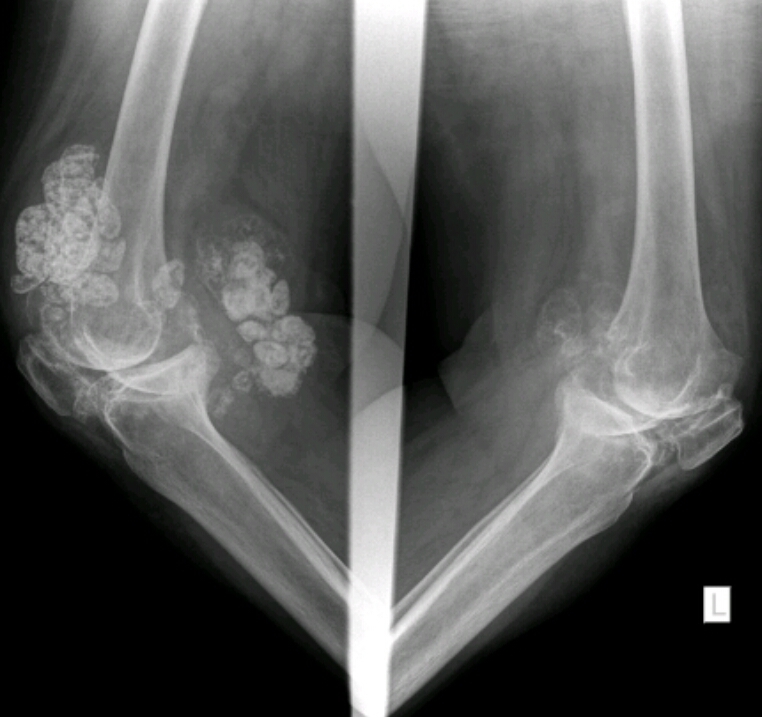

Name the disease

Synovial osteochondrometaplasia

AKA intraarticular joint mice